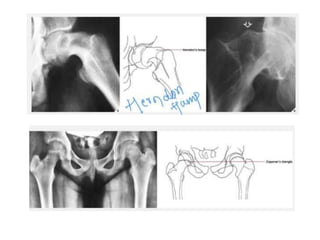

SCFE

Congenital coxa vara

Hilgenreiner’s epiphyseal angle

Head at RiskSign 1. ‘V’ sign 2. Lateral Epiphyseal calcification 3. Lateral subluxation 4. Horizontal Epiphysis 5. Metaphyseal Changes any 2 out of 5